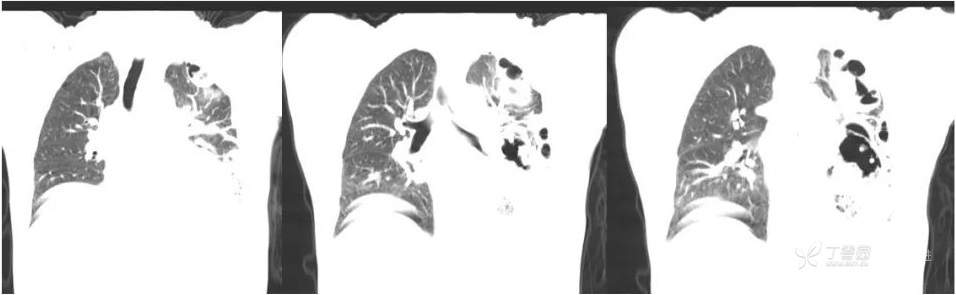

冠状位肺窗重建